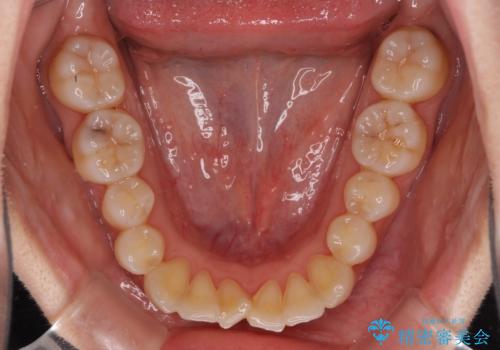

前歯のクロスバイト インビザラインによる矯正治療

- 上下のクロスバイトと前歯のデコボコを気にして来院された患者様です。

インビザラインを用い、IPR(歯と歯の間を削る)と歯列全体を拡大させることで、歯並びを整えていくこととしました。

治療を急いでいらっしゃらなかったため、のんびりと治療を進めていきました。3年以上の期間を要しましたが、きれいな口元に仕上がりました。